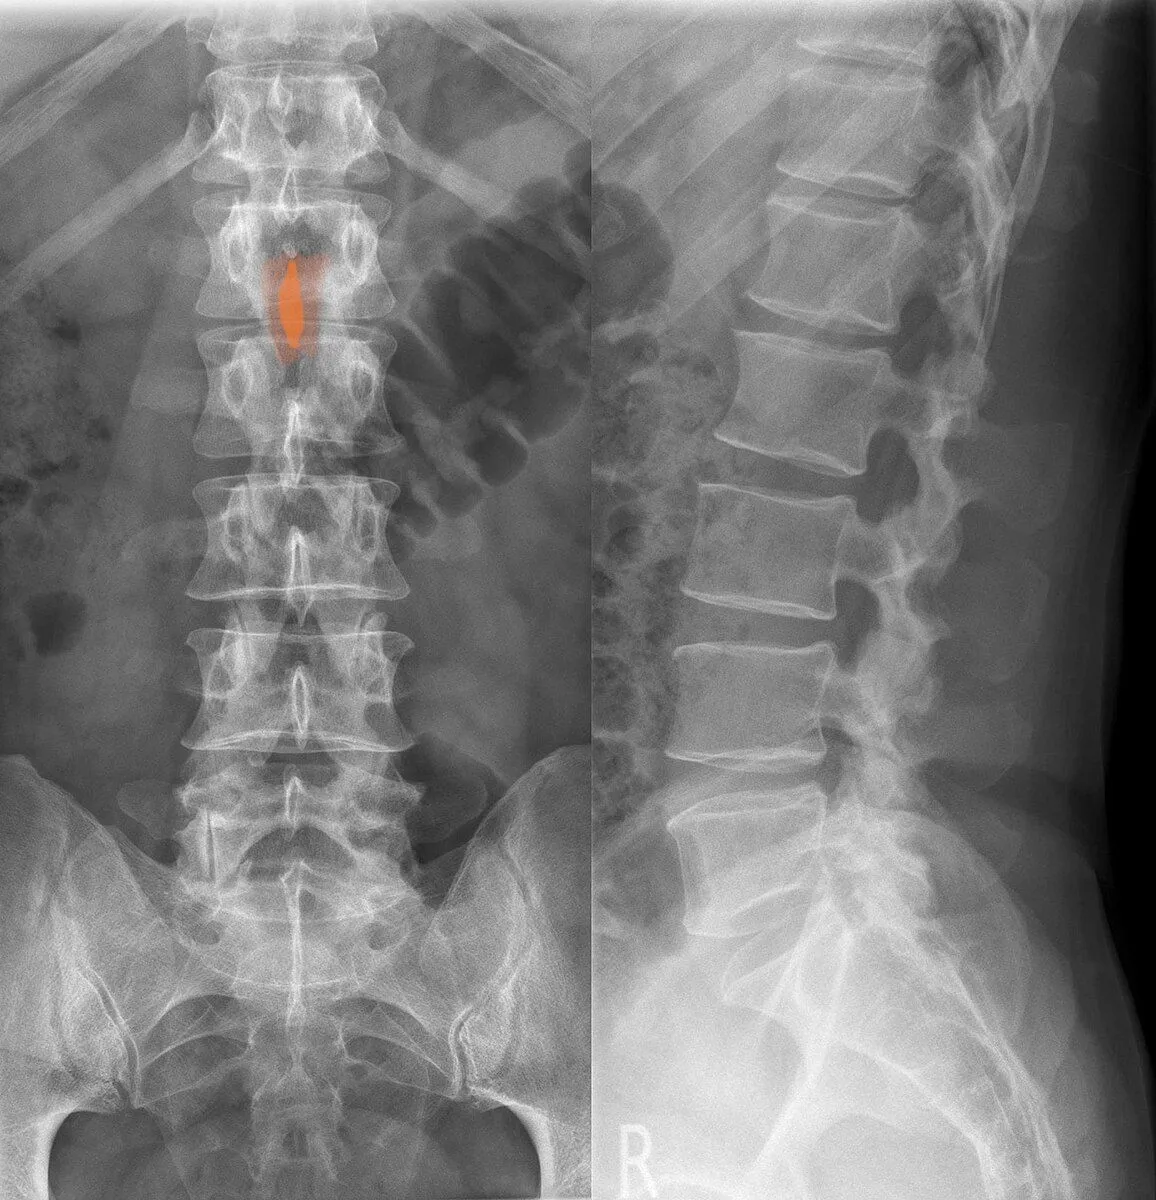

6. Sacroiliac Joint (SI Joint) Fusion

The sacroiliac joint links the iliac (pelvic) bones to the sacrum (lowest part of spine above tailbone). This joint absorbs shock, protecting the spine from impact forces. When injured or deteriorated, it causes pain in buttocks, low back, and legs.

During SI joint surgery, the patient lies face down while the surgeon makes a small incision on the side of the buttocks. A bone graft is placed between the ilium and sacrum with the intention of connecting the two bones, relieving joint pain.

The bone graft (usually taken from hip bone) doesn’t automatically fuse bones. Over time, it grows to create one immobile joint. The bone graft continues solidifying for up to 12 months, though patients feel immediate relief.